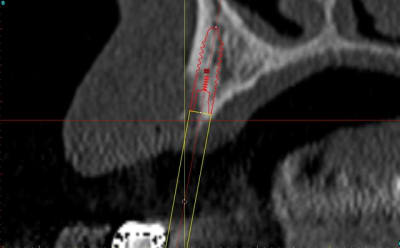

mise en place du conique lisse

contrôle, axe et profondeur

après les implants lisses coniques il faut passer aux lisses Axioms

donc Ostéotomes impactés pour mettre la corticale du sinus aux dimensions et pousser la membrane (et l'éponge)

en 25 pour le moment l'axiom lisse est de 3.4mm

puis les Axioms avec un 4 mm en 25

contrôle de l'os vestibulaire (différents contraste pour juger de la "minceur" de l'os :-)))